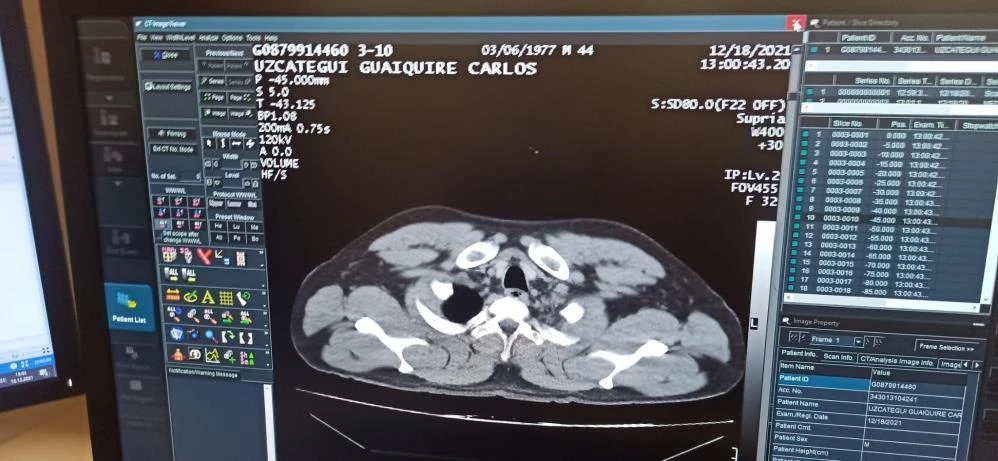

Hastaneye götürülen C.M.U.G'un hastanede yapılan tomografi kontrolünde mide ve bağırsaklarında 12 adet kapsül tespit kokain tespit edilmesini üzerine şahıs ameliyata alındı.